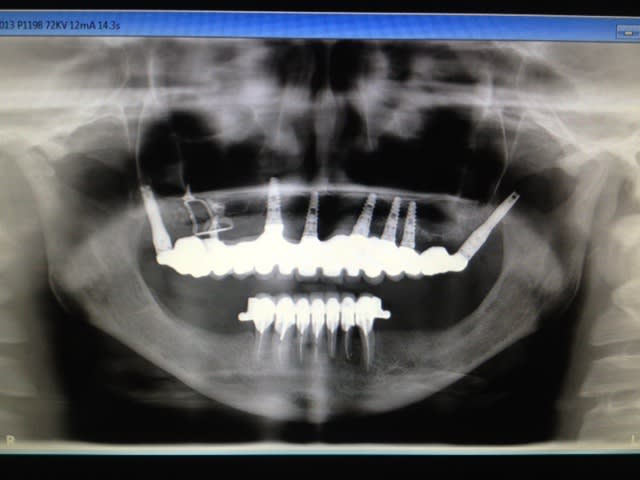

reprise d'une barre all on five:

au départ all on five réalisé par un confrère, à l'arrivée all on three après per de 2 implants !

repris en basale avec 2 plaques et un axial supplémentaire